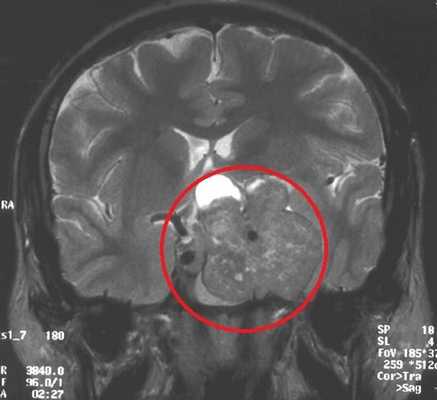

МРТ гипофиза. На МР-томограмме определяется гигантское образование неоднородной структуры (обведено) — макроаденома гипофиза.

Норма размер гипофиза на МРТ снимке